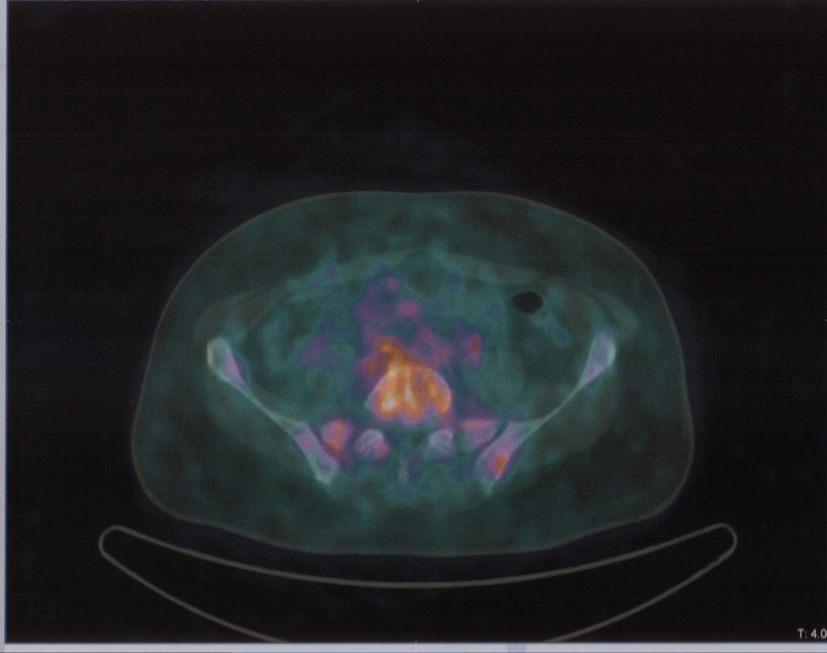

In August 2013, the patient referred to our hospital to investigate “in vivo” SSTR receptorial status. PET/CT evidenced several areas of increased uptake scattered through the whole skeleton, corresponding on CT with mostly mixed osteoblastic/osteolytic metastases (Fig. 3, 4).

![]() Click for large image | Figure 4. Same patient and acquisition parameters of Fig. 3. 68Ga-DOTANOC transaxial PET/CT at the level of fourth lumbar vertebra showing increased uptake of the radiopharmaceutical in a mixed metastasis. |